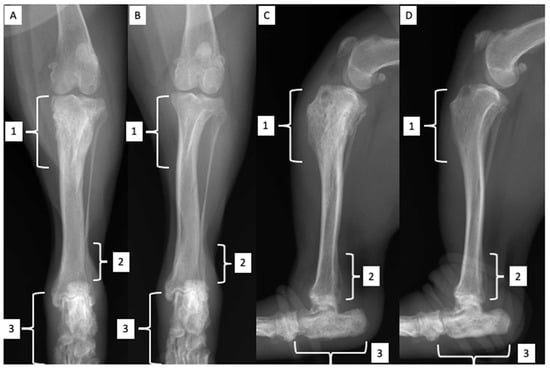

2.2. Orthopedic Examination and Radiological Findings